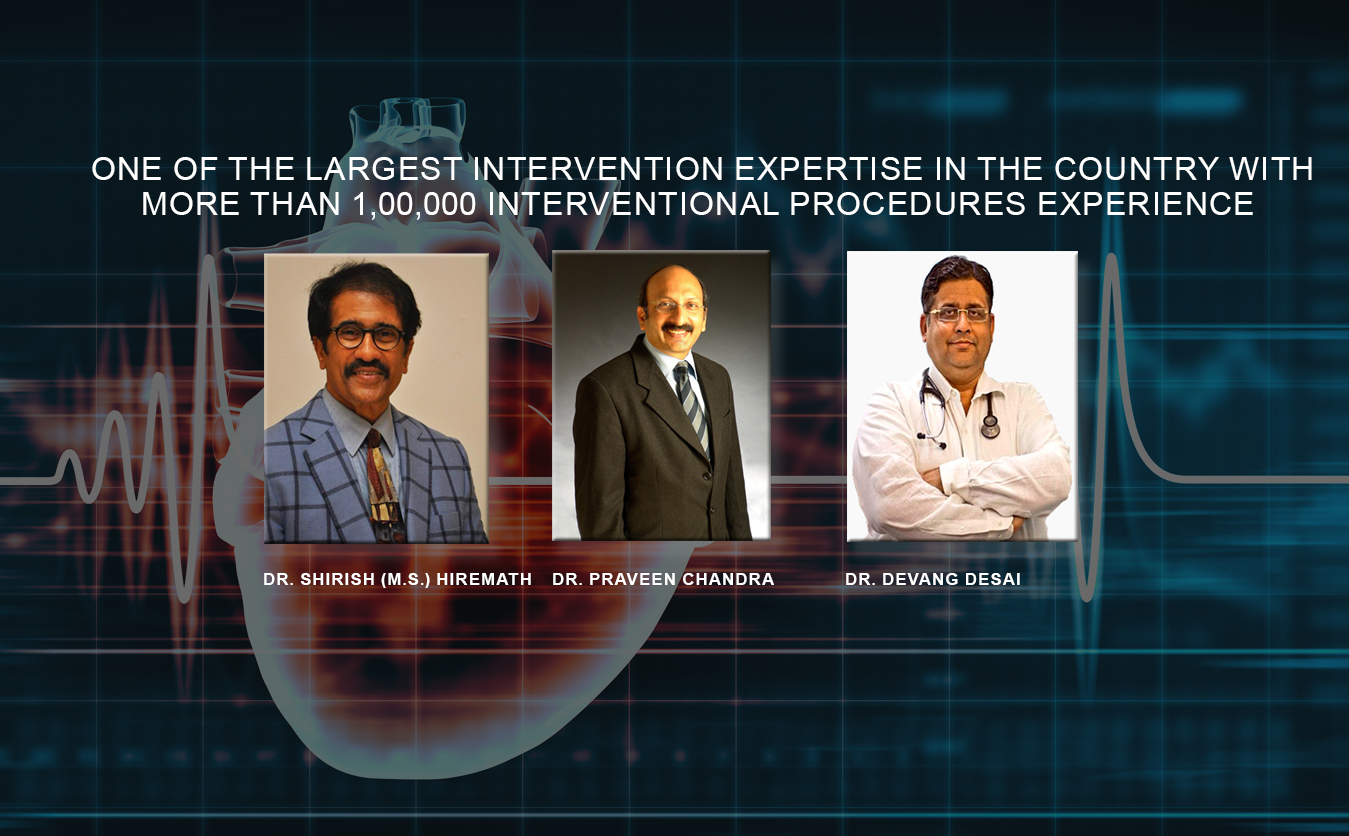

Dr. Praveen Chandra

Conferred with the most prestigious Padma Shri Award in 2016Recognized as one of the key leaders in the country & is proficient in lot of new devices & technologies, from Delhi - North India

Dr. Shirish (M.S.) Hiremath

President – Cardiological Society of IndiaOne of the most experienced Cardiologist in the country from Pune, Maharashtra

Dr. Devang Desai

One of the leading Interventional Cardiologist & Cardiovasular specialist from Surat, Gujarat